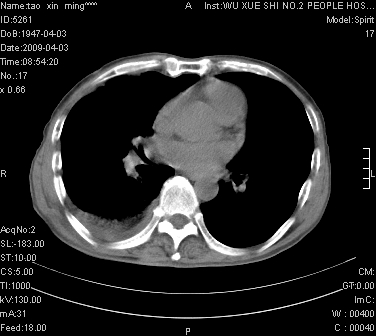

男.62.咯血.胸痛

考虑;肺癌  胸膜转移

肺出血,周围型肺癌,右侧胸腔积液

考虑肺癌可能性大

考虑肺癌并右侧胸腔积液肺出血

1)考虑右肺下叶周围型肺癌,并右肺下叶肺出血。2)右侧少量胸腔积液。

1)考虑右肺下叶周围型肺癌。2)右侧少量胸腔积液。